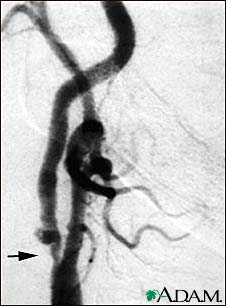

Carotid stenosis, X-ray of the right artery

This is an angiogram of the right carotid artery showing a severe narrowing (stenosis) of the internal carotid artery just past the carotid fork. There is enlargement of the artery or ulceration in the area after the stenosis in this close-up film. Note the narrowed segment toward the bottom of the picture.